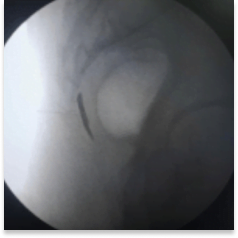

This procedure is performed with the patient in a prone position on the Operating table. Some practitioners like to prepare patients with laxatives the night before. With fluoroscopic guidance, a thin spinal needle is advanced through the sacrococcygeal hiatus. Needle placement is confirmed and dye spread is checked under fluoroscopy. Medication is delivered at the site of the Ganglion of Impar. This helps in blocking the sacrococcygeal plexus of nerves.

AP View

Intraop fluoroscopy image

of ganglion impar injection

Intraop fluoroscopy image of contrast dye injection for confirmation of placement of needle